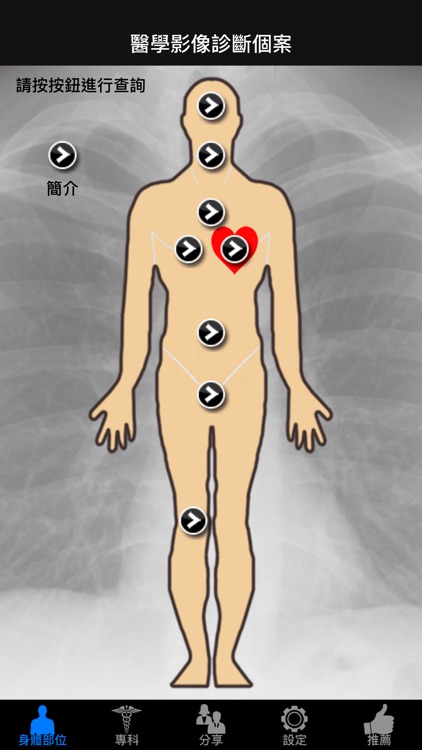

醫學影像診斷個案

App Screenshots

功能簡介:

1. 以層次的方式,即選擇身體部位/醫學專科,再從該部位/專科的列表中,選擇各種視頻。